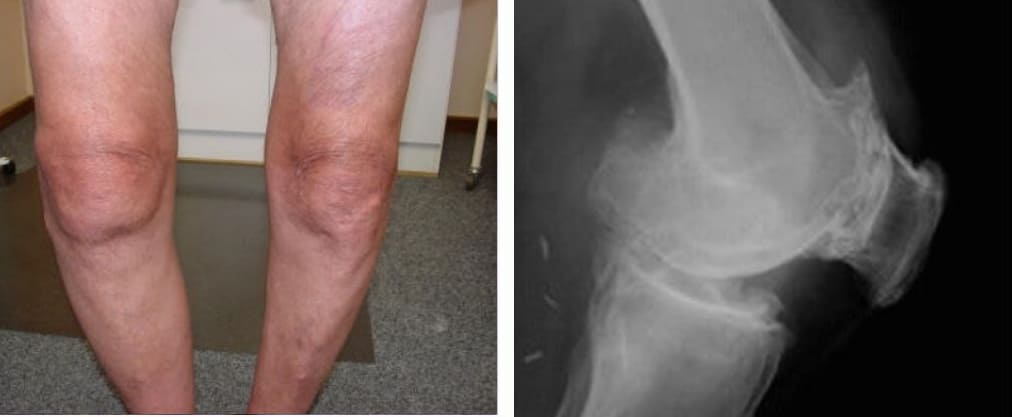

Quyidagi suratlarga qarang. Belgilarga e’tibor bermaganlarning boshiga nimalar tushganini ko‘ring. Bugun bu odamlar umidsiz holatda, ularning ko‘pchiligida yordam so‘rashga ham odam qolmagan. Siz ham o‘zingizga bunday taqdirni ravo ko‘rasizmi?

Tizza bo‘g‘imlarining atrofiyasi va kuchli qiyshayishi, hatto eng kichik harakatda ham doimiy, o‘tkir og‘riq.

Ayol, 42 yosh. Tizza bo‘g‘imining og‘ir deformatsiyasi, tizzalarning qiyshayishi. To‘liq tiklanish uchun ikki kurs Joint Solve kerak bo‘ldi.